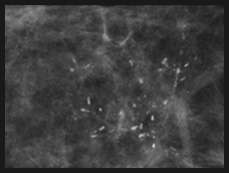

Fine Pleomorphic Calcifications

Fine pleomorphic calcifications: calcifications of different shapes and sizes, with a size between 0.5 and 1.0 mm, smaller than coarse heterogeneous calcifications. These are considered a 4B category finding.